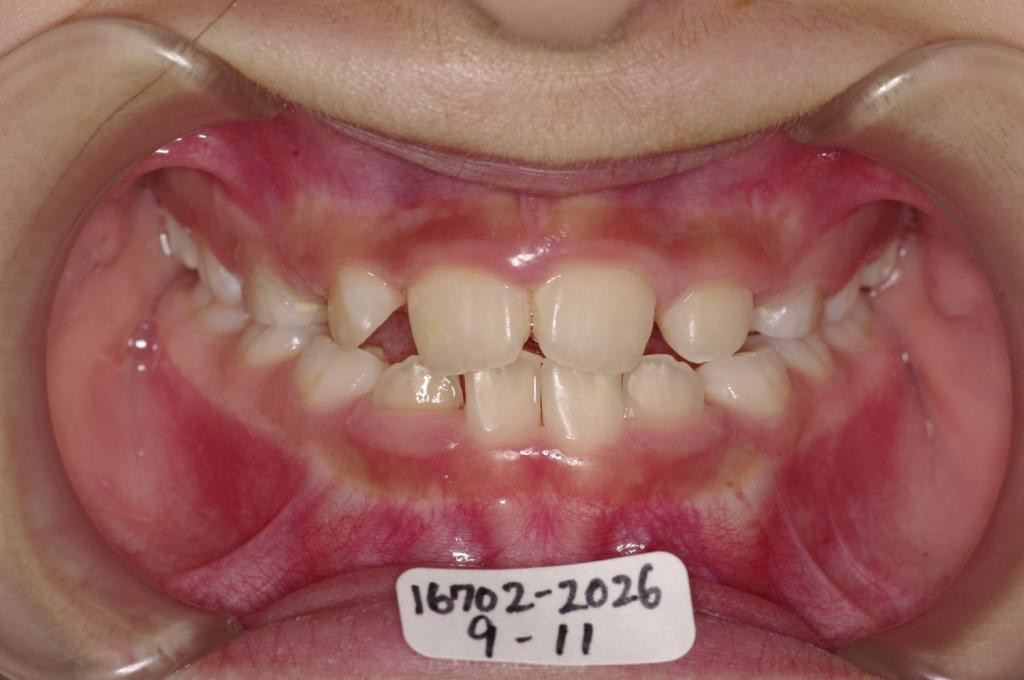

子供の矯正治療

(治療期間、治療前後写真、治療方法、費用)WORKS

下記の実績データをクリックして頂くと「性別」、「治療開始年齢」、「治療終了年齢」、「治療方法(矯正治療装置写真含む)」、「治療終了までの費用」など、詳細な矯正治療データをご覧頂けます。